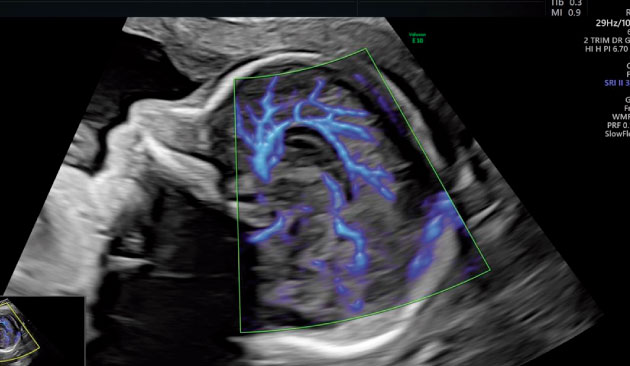

Ultrasonidos de última Generación

Ecografías en el embarazo

Expertos en detección temprana de anomalías. Brindamos una gama completa de Ultrasonidos Fetales y Ecografías 7D:

Viabilidad, Genética, Morfológica, Crecimiento Doppler, Ecocardiografía fetal, Neurosonografía fetal, etc.